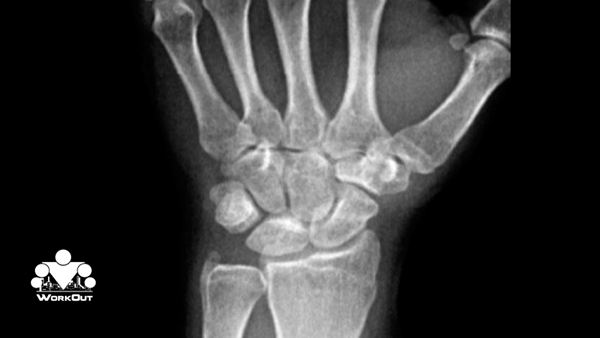

Во-первых, запястья. Если посмотрите на рентген запястного сустава, кисти, то вы увидите огромное количество костей.

Когда вы становитесь на руки, вы давите всем своим телом на очень маленькую площадь. И в случае, если она не обладает должной силой, чтобы стабилизировать, чтобы распределять нагрузку, балансировать вашим весом, то у меня очень плохие новости. Можете погуглить, что такое гигрома, и я уверен, что вам не захочется её получить. Поэтому, если вы не можете отжаться от пола 50, а лучше 100 раз, то даже не пытайтесь сделать стойку. Серьезно. Ваши запястья будут вам очень благодарны, если вы не будете совершать такие глупости.